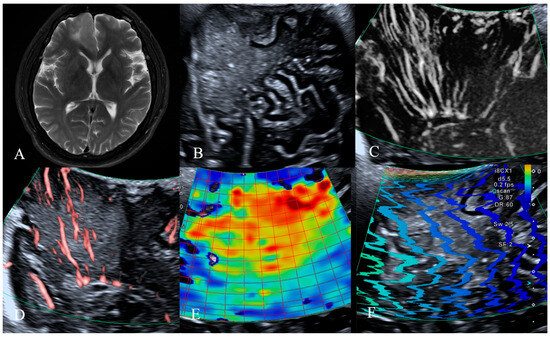

| HGG (n, %) | LGG (n, %) | p Value | |

|---|---|---|---|

| Tumor Vessels | 0.001 * | ||

| Dilated and bent vessels | 18 (37.5%) | 2 (4.2%) | |

| Straight and branching vessels | 7 (14.6%) | 13 (27.1%) | |

| Avascular | 5 (10.4%) | 3 (6.3%) | |

| Vessels Around the Tumor | 0.001 * | ||

| Distorted and surrounding vessels | 20 (41.7%) | 2 (4.2%) | |

| Straight and penetrating vessels | 6 (12.5%) | 9 (18.8%) | |

| Normal cerebral vessels | 4 (8.3%) | 7 (14.6%) | |

| Total | 30 (62.5%) | 18 (37.5%) |

| LGG (kPa) | HGG (kPa) | t’ | p Value | |

|---|---|---|---|---|

| Intratumoral tissue | 23.4 ± 11.6 | 12.1 ± 13.7 | 2.937 | 0.005 * |

| Peritumoral tissue | 13.2 ± 4.6 | 10.4 ± 3.6 | 2.305 | 0.026 * |

| t’ | 3.499 | 0.644 | ||

| p value | 0.001 * | 0.524 |